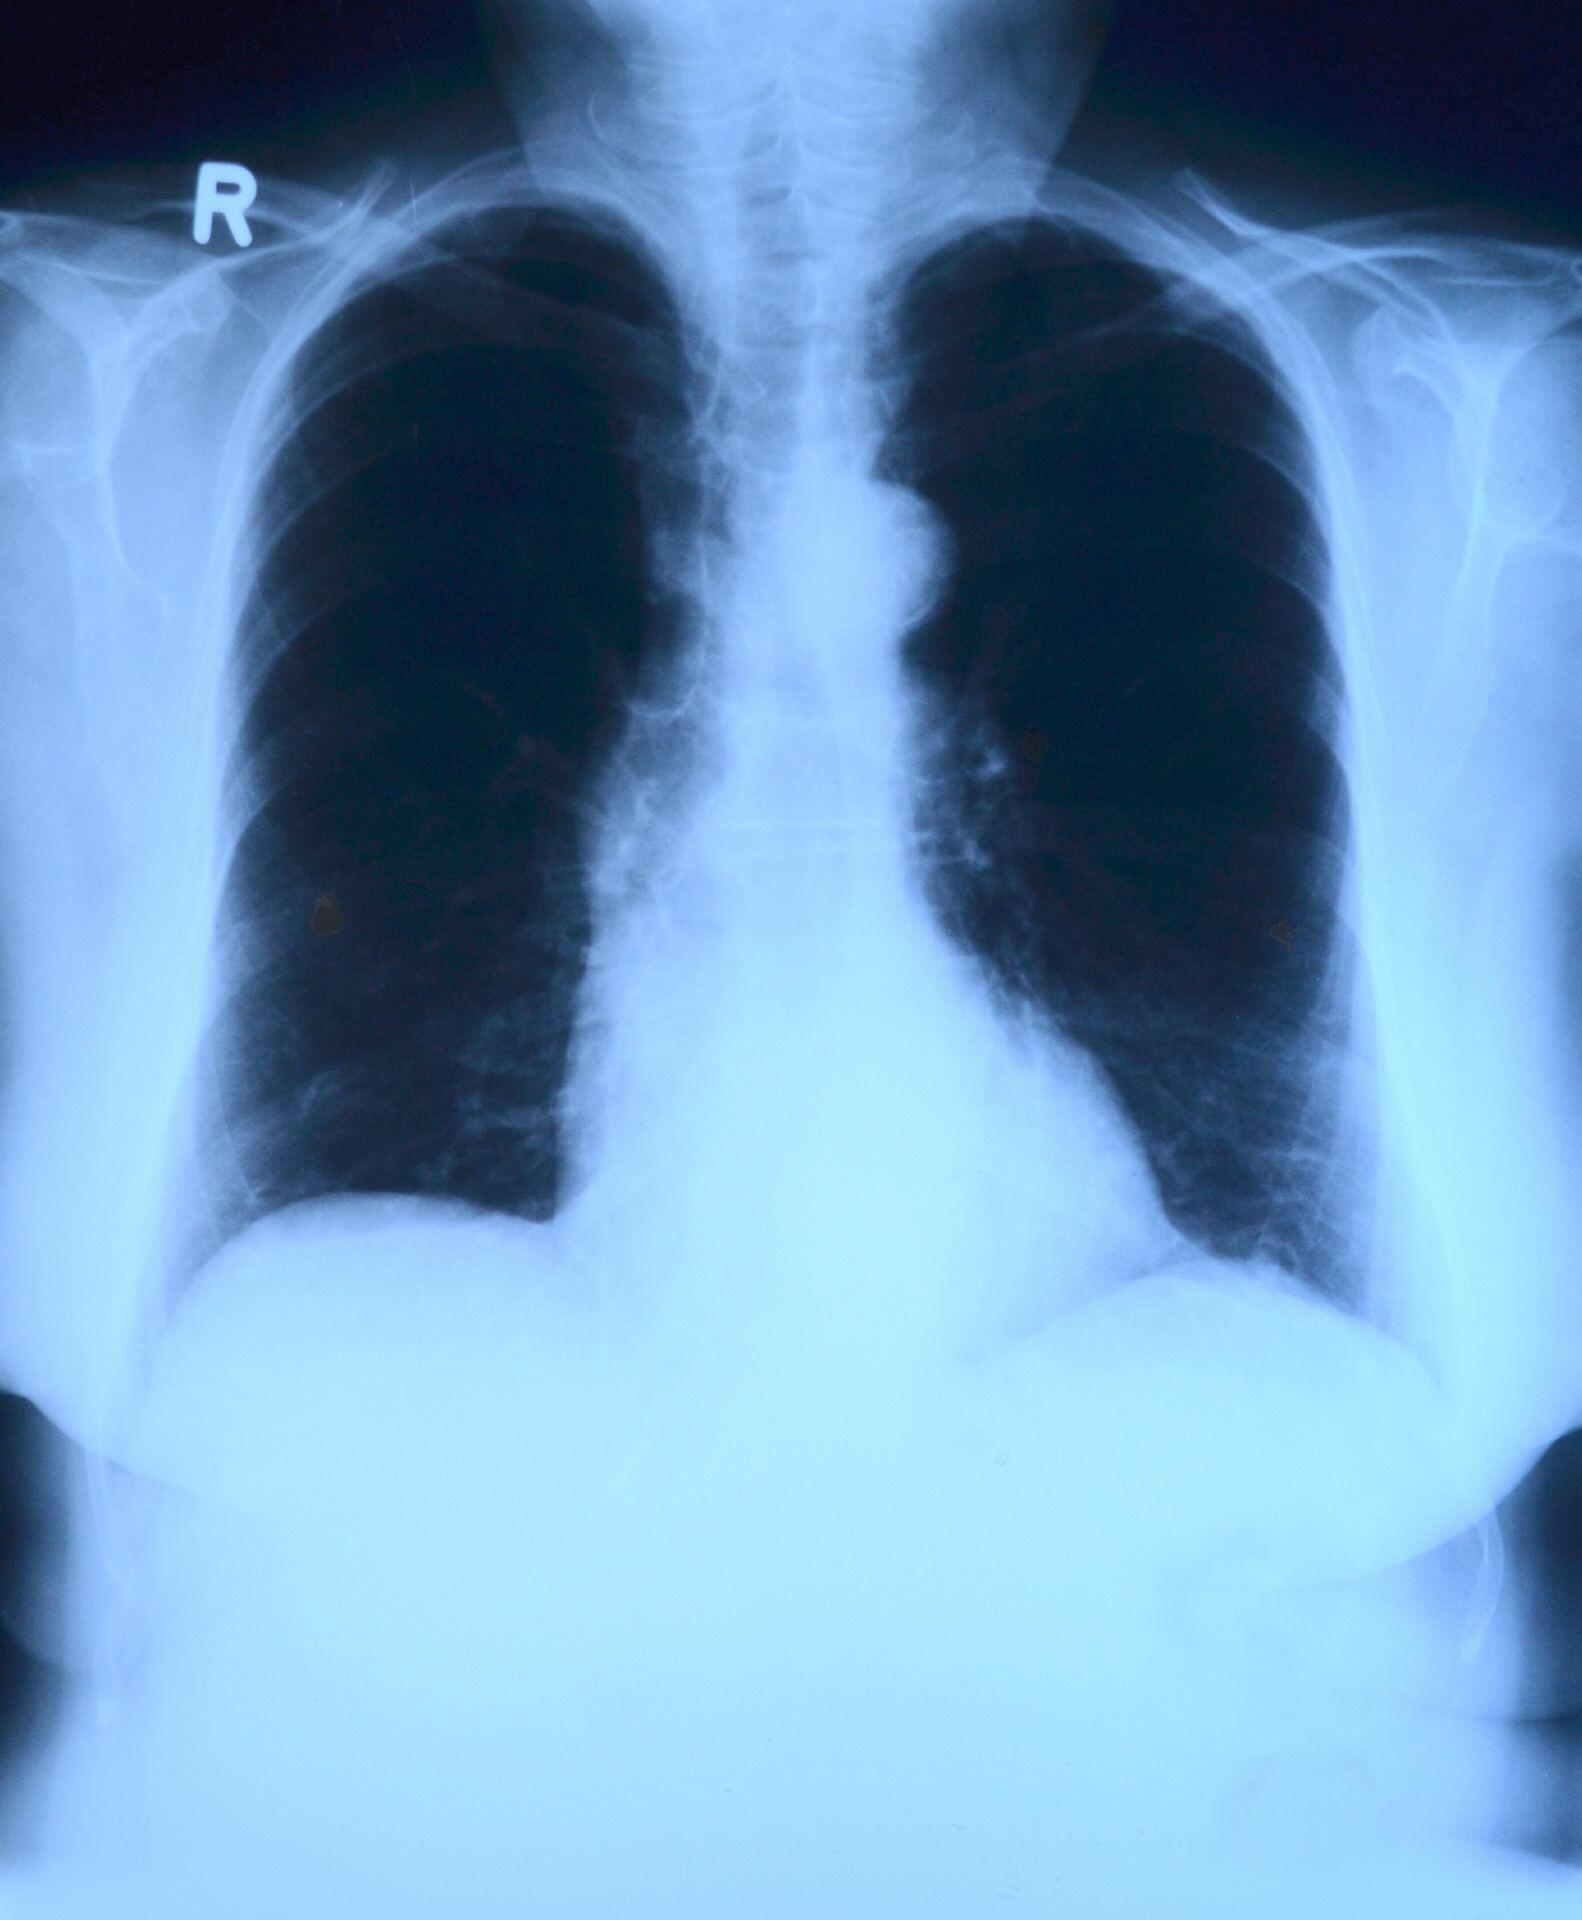

From www.svuhradiology.ie

Lung cancer in patient with previous asbestos exposure Radiology at What Does Asbestos Look Like In The Lungs — asbestosis is a chronic lung disease caused by exposure to asbestos fibers. It causes scarring and inflammation of the lungs, making it hard to breathe. asbestosis is a lung disease caused by breathing in asbestos dust and fibers. asbestosis is a chronic lung condition caused by inhaling asbestos fibers that cause inflammation and scarring of lung.. What Does Asbestos Look Like In The Lungs.

From www.steadyhealth.com

Suspicious Densities On The Lungs Related To A Lung Parenchyma Due To What Does Asbestos Look Like In The Lungs learn about the types, risks, and symptoms of asbestos, a mineral that can cause serious lung problems if inhaled. Learn about the symptoms, diagnosis and treatment options,. asbestosis is a chronic lung condition caused by inhaling asbestos fibers that cause inflammation and scarring of lung. — asbestos exposure can increase your risk of developing lung cancer, especially. What Does Asbestos Look Like In The Lungs.

From www.learningradiology.com

Learning Radiology AsbestosRelated Pleural Disease, asbestosis What Does Asbestos Look Like In The Lungs asbestosis is a lung disease caused by breathing in asbestos dust and fibers. — asbestosis is a condition that develops when you inhale asbestos fibers and they cause scarring in your lungs. — asbestos exposure can increase your risk of developing lung cancer, especially if you smoke. asbestosis is a chronic lung condition caused by inhaling. What Does Asbestos Look Like In The Lungs.